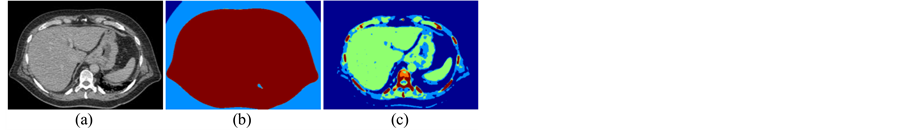

Indeed, the original TSMO method [17] was introduced to accelerate computation without changing the results of a traditional Otsu’s method [18] . Conversely, these results are not good to present hard-tissue regions in our data sets as shown in Figure 5. Therefore, we need a range-constraint to improve the results. Indeed, an assignment of a range-constraint is often mentioned [19] - [21] , but it depends on a specific pattern of gray-inten- sities in a given image. In this study, we present a simple idea to define a range constraint by cutting gray intensities below the water (0 HU). The CT images describe gray intensities as CT standard numbers in the Houns-

Figure 5. An example of five-class clustering on a 16-bits CT image (a) using TSMO method (b) and including a proposed range-constraint (c).